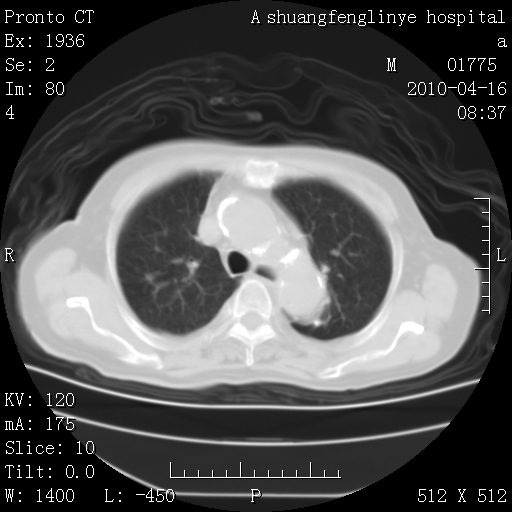

考虑左肺上叶增殖灶、纤维灶。

支持结核

慢支肺气肿,左上陈旧性结核,主动脉冠脉钙化

1)左肺上叶结核(纤维、增殖病灶)。2)冠状动脉及主动脉钙化。

1)左肺上叶结核(纤维、增殖病灶)。2)冠状动脉及主动脉钙化。肺动脉高压